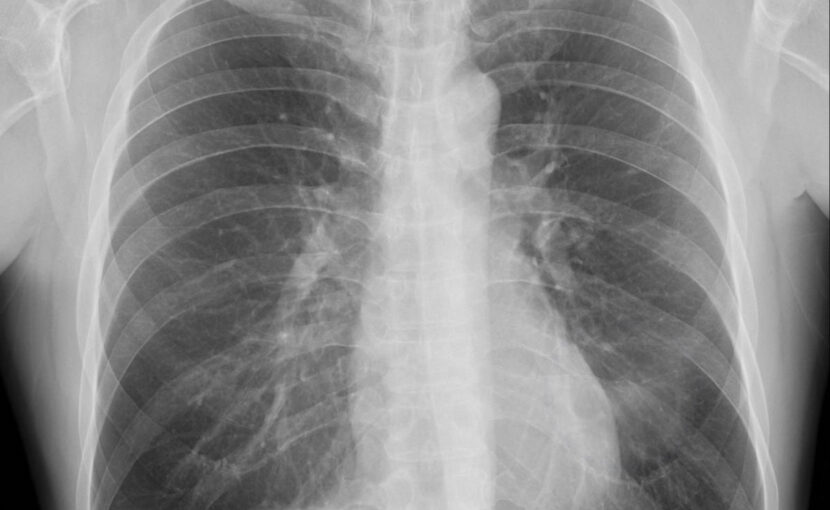

[粉じん作業についての職歴の調査及びエックス線写真による検査]

じん肺用の撮影条件を元に撮影をします。

一般的なレントゲン撮影と同様に息どめ後5秒以内に撮影が完了しますし、放射能も他のレントゲン撮影法に比べて低くなりますので、侵襲性は低いです。

この写真撮影で初見が見られた場合には、各医療機関にて肺機能検査などの追加検査を受けていただきます。